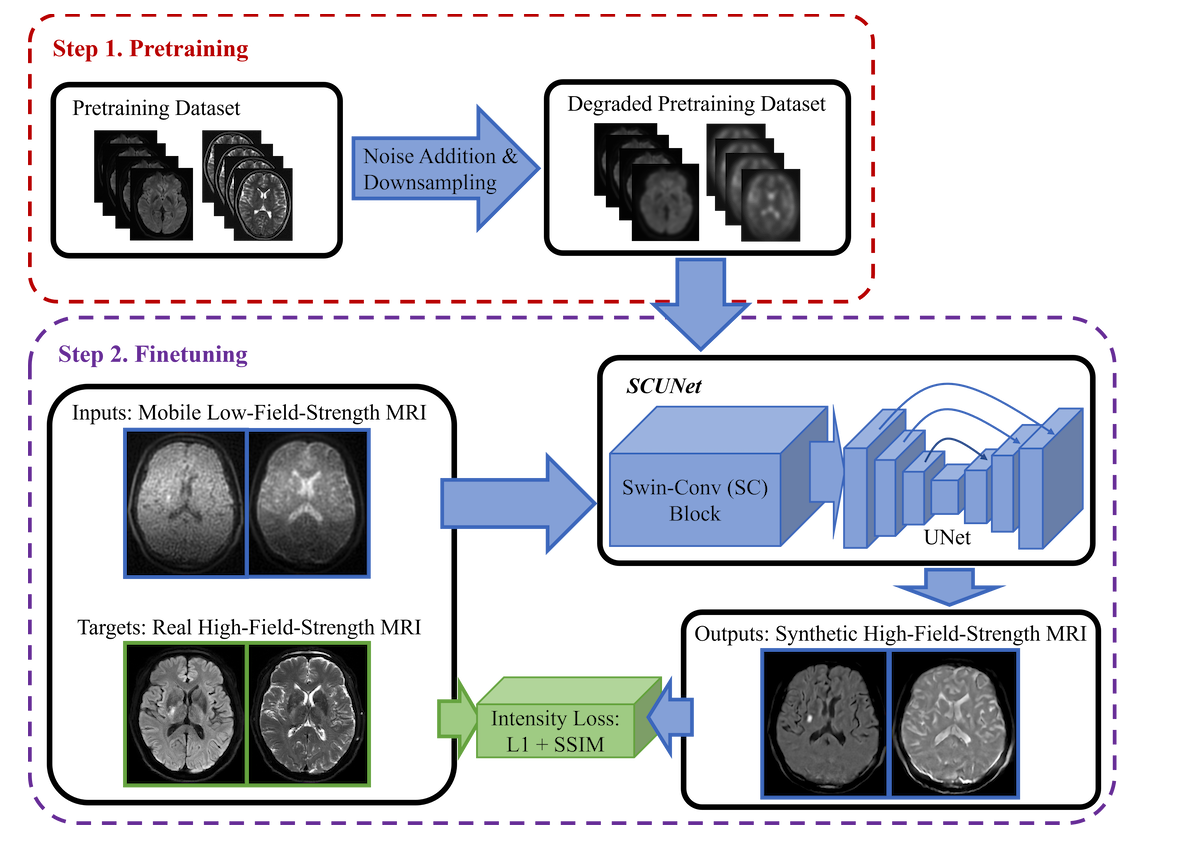

Quantitative Ischemic Lesions of Portable Low-Field-Strength MRI Using Deep Learning-Based Super-Resolution

This is the official implementation of Quantitative Ischemic Lesions of Portable Low-Field-Strength MRI Using Deep Learning-Based Super-Resolution. This project utilizes the Swin-Conv-UNet (SCUNet) denoising network to enhance low field images, making them comparable to high field images.